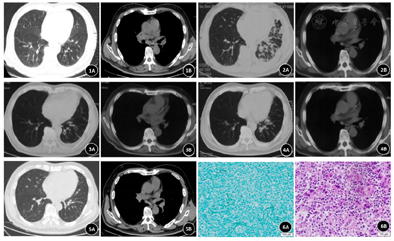

患者,66岁,男性,因"反复咳嗽18月"于2020年11月1日收入我院呼吸与危重症医学科。患者自2019年5月起出现阵发性干咳,PET-CT(图1):两侧肺门、纵隔、右侧锁骨上窝、肝门区、腹膜后多发淋巴结肿大,糖代谢增高。2019年9月外院行胸腔镜检查,胸膜病理:多灶性肉芽肿性病变,其病变可见中央坏死,周围可见上皮细胞及多核巨细胞,组织改变为肉芽肿性炎,2次抗酸(+),六胺银(-),倾向结核。纵隔淋巴结病理为肉芽肿性炎,倾向结核。诊断为肺结核合并淋巴结结核,予利福平0.45g qd、异烟肼0.3g qd、吡嗪酰胺1.5g qd、乙胺丁醇0.75g qd治疗9月后,患者症状无改善,复查胸部增强CT(图2)两肺门、纵隔淋巴结增大并融合。2020年6月19日气管镜肺活检组织病原体宏基因组高通量测序(mNGS):结核分枝杆菌复合群(序列数19),奥布分枝杆菌(序列数302),星形奴卡菌(序列数64),病理:肺间质性炎症,未见明确肉芽肿病变及肿瘤。2020年7月10日颈淋巴结培养:马尔尼菲篮状菌,病理:淋巴结肉芽肿性炎。胸部CT(图3):肺部病变较前好转,但仍多发淋巴结肿大。肺组织mNGS:奴卡菌,予复方磺胺甲噁唑(1.2g qid)、利奈唑胺(0.6g q12h)治疗3个月后复查胸部CT(图4):肺部病变较前吸收,但淋巴结肿大改善不明显,于2020年11月1日收住我院呼吸与危重症医学科。家族史、冶游史无特殊。

予伏立康唑0.2g q12h治疗2月后咳嗽消失,双侧颈部、右耳前、右耳下、枕后、右滑车、左耳后淋巴结及右侧肘部皮下肿大淋巴结消失。复查胸部CT(图5):双肺散在炎症,双侧腋窝林巴结肿大,右侧为著约33mm × 22mm。患者右侧腋窝淋巴结明显疼痛,考虑仍存在奴卡菌感染可能,加用利奈唑胺0.6g q12h口服2月余。期间数次尝试停用利奈唑胺,但停药时间不超过3天,患者右侧腋窝淋巴结又开始明显疼痛,重新服用利奈唑胺后右侧腋窝淋巴结疼痛明显缓解。复查抗IFN-γ自身抗体仍为强阳性,签署超说明书用药及知情同意后遂予利妥昔单抗600 mg治疗。

血常规:白细胞计数14.55×109/L,血红蛋白浓度125g/L,血小板计数347×109/L,中性粒细胞比值72.50%,淋巴细胞比值15.60%,淋巴细胞绝对值2.27×109/L,超敏C反应蛋白(hs-CRP)62.8mg/L。降钙素原、1,3,β-D葡聚糖(G)试验、半乳甘露聚糖(GM)试验正常。痰涂片:较多G+球菌,少量G-球杆菌和G-杆菌。肺泡灌洗液(BALF)利福平耐药实时荧光定量核酸扩增检测(X-pert)、气管镜取痰涂片及培养阴性。纵隔淋巴结病原体mNGS:人类γ疱疹病毒4型(序列数5);缺陷乏养菌(序列数3)。纵隔淋巴结病理聚合酶链反应(PCR):阴性。淋巴细胞亚群+绝对计数: CD3+T细胞54.11%(50-84),CD3+T绝对计数1015.64 cells/uL(955-2860),CD3+CD4+辅助/诱导性T细胞31.65%(27-51),CD3+CD4+绝对计数593.94 cells/uL(550-1440),CD3+CD8+抑制/细胞毒性T细胞21.68%(15-44),CD3+CD8+绝对计数406.85 cells/uL(320-1250),CD3-CD19+总B细胞2.61%(5-18),CD3-CD19+绝对计数49.00 cells/uL(90-560),CD3-CD16+56+NK细胞42.64%(7-40),CD3-CD16+56+绝对计数800.33 cells(150-1100),CD4+/CD8+Th/Ts比值1.46%(0.68-2.4)。免疫球蛋白A 5.04g/L(0.70-4.5),免疫球蛋白G 24.85g/L(8-18),免疫球蛋白M 1.034g/L(0.4-2.5),补体C3 1.57g/L(0.8-1.81),补体C4 0.67g/L(0.15-0.57)。抗IFN-γ自身抗体滴度148000ng/mL(OD:4,强阳性),STAT1-PI10 30.79。右颈部淋巴结病理(图6):淋巴结肉芽肿性炎症,符合马尔尼菲篮状菌感染。人类γ疱疹病毒4型和缺陷乏养菌均为人类呼吸道和口腔可定值的病原体,且其序列数低,与患者临床症状不相符,故我们认为两种病原体并非致病菌。